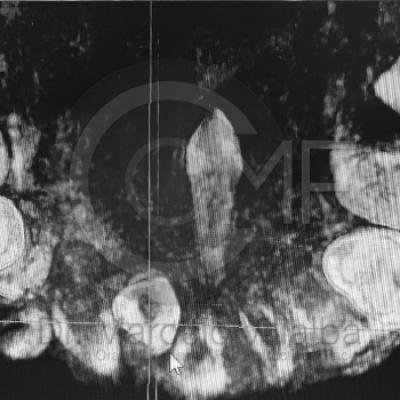

Dientes Supernumerarios